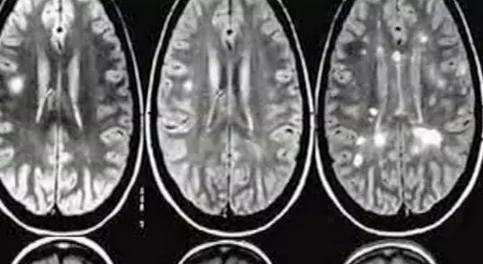

多发性硬化症(Multiple Sclerosis)是一种慢性中枢神经系统疾病,它影响神经元传递的信息,造成大脑和脊髓的斑块性神经髓鞘的破坏,造成多部位的僵硬或丧失功能。其本质上是一种自体免疫疾病,身体的免疫系统错误地攻击名为髓磷脂的脑神经元脂质外层,这种情形若持续发生,便会导致瘫痪。

此病的平均发病年龄在20至40岁,是年轻人致残的主要疾病,女性多于男性,全世界有大约230万人受这种神经疾病影响,以前一直是不治之症。